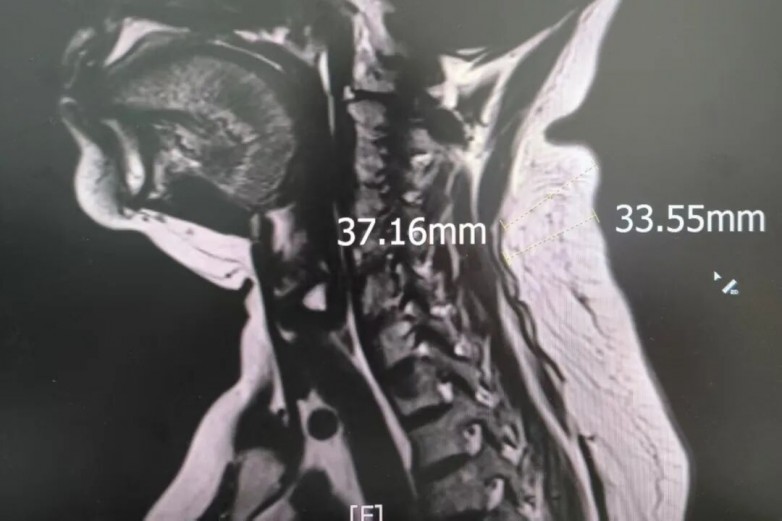

微创水动力切除术显成效,医院帮助患者告别20年“富贵包”困扰